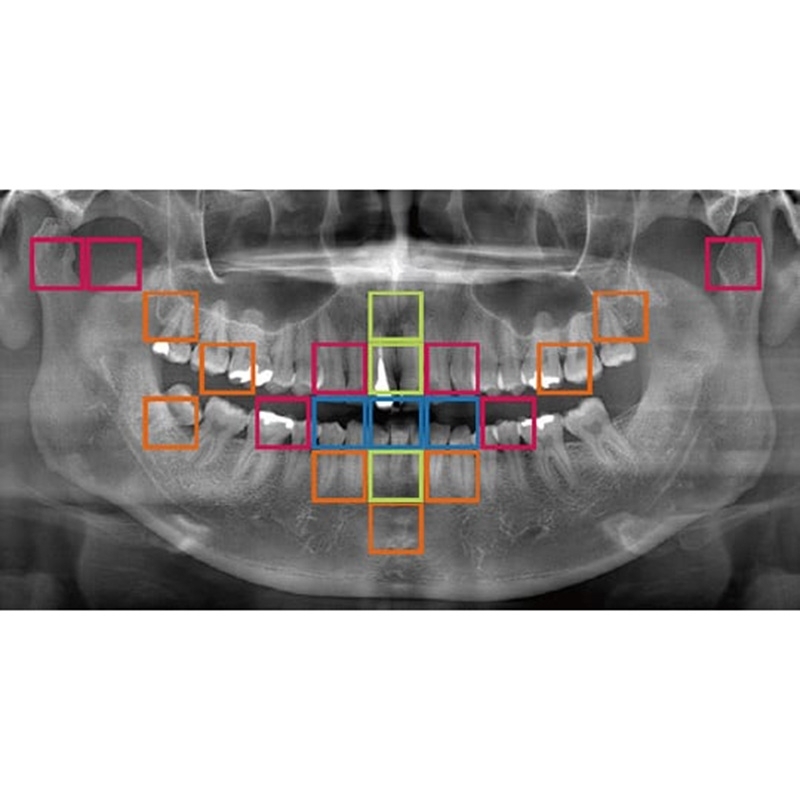

Information / DémonstrationPanoramique 2D

Veraview (IC5 HD) Données Techniques

Mode High-Speed - 5,5 sec./192 µm

Mode High-Definition - 10 sec./96 µm - Visée laser: